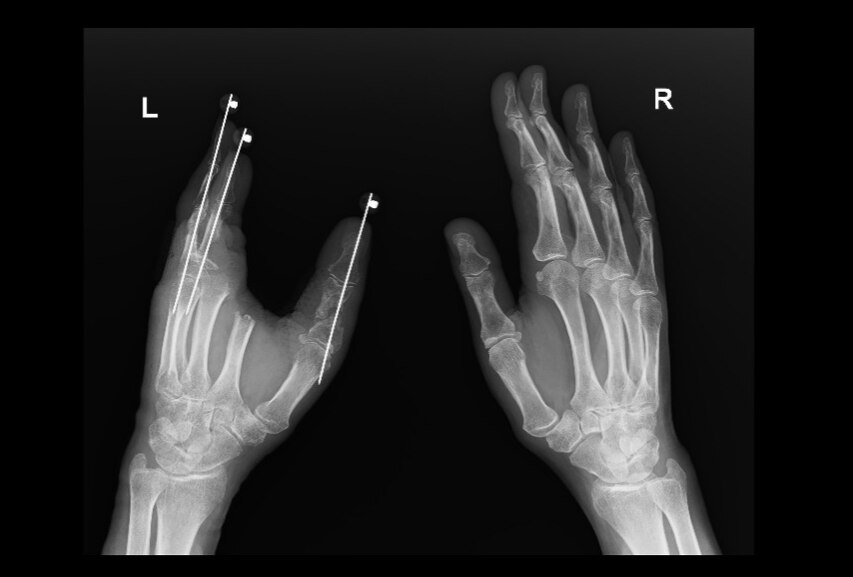

An X-ray showing Ms Strange's injured left hand. (Supplied: Kaye Strange )

Ms Strange spent 10 days in the hospital and underwent five operations.